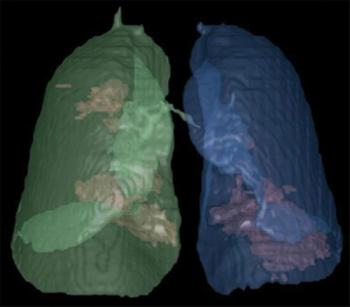

Scans reveal differences in lesion locations, mucoid impaction, and pleural effusion.